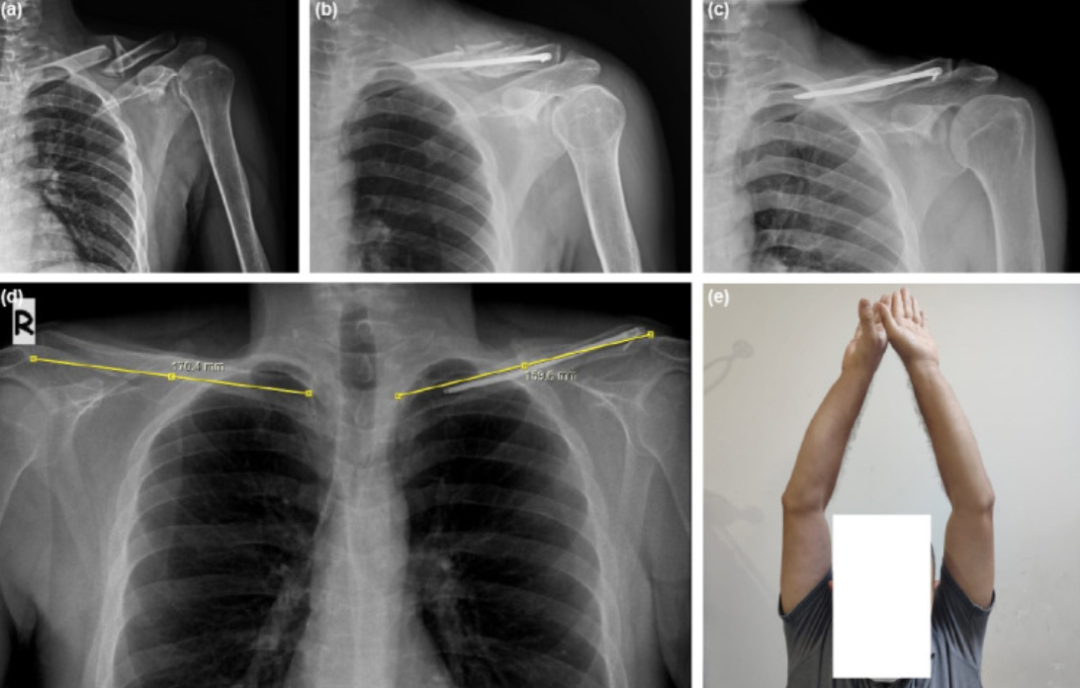

(a, b)一名38岁男性左侧锁骨粉碎性骨折术前及术后8周前后位X光片;(c, d)术后2年骨折愈合后前后位X光片,显示创伤后短缩6.3%;(e)同一患者的临床图像。